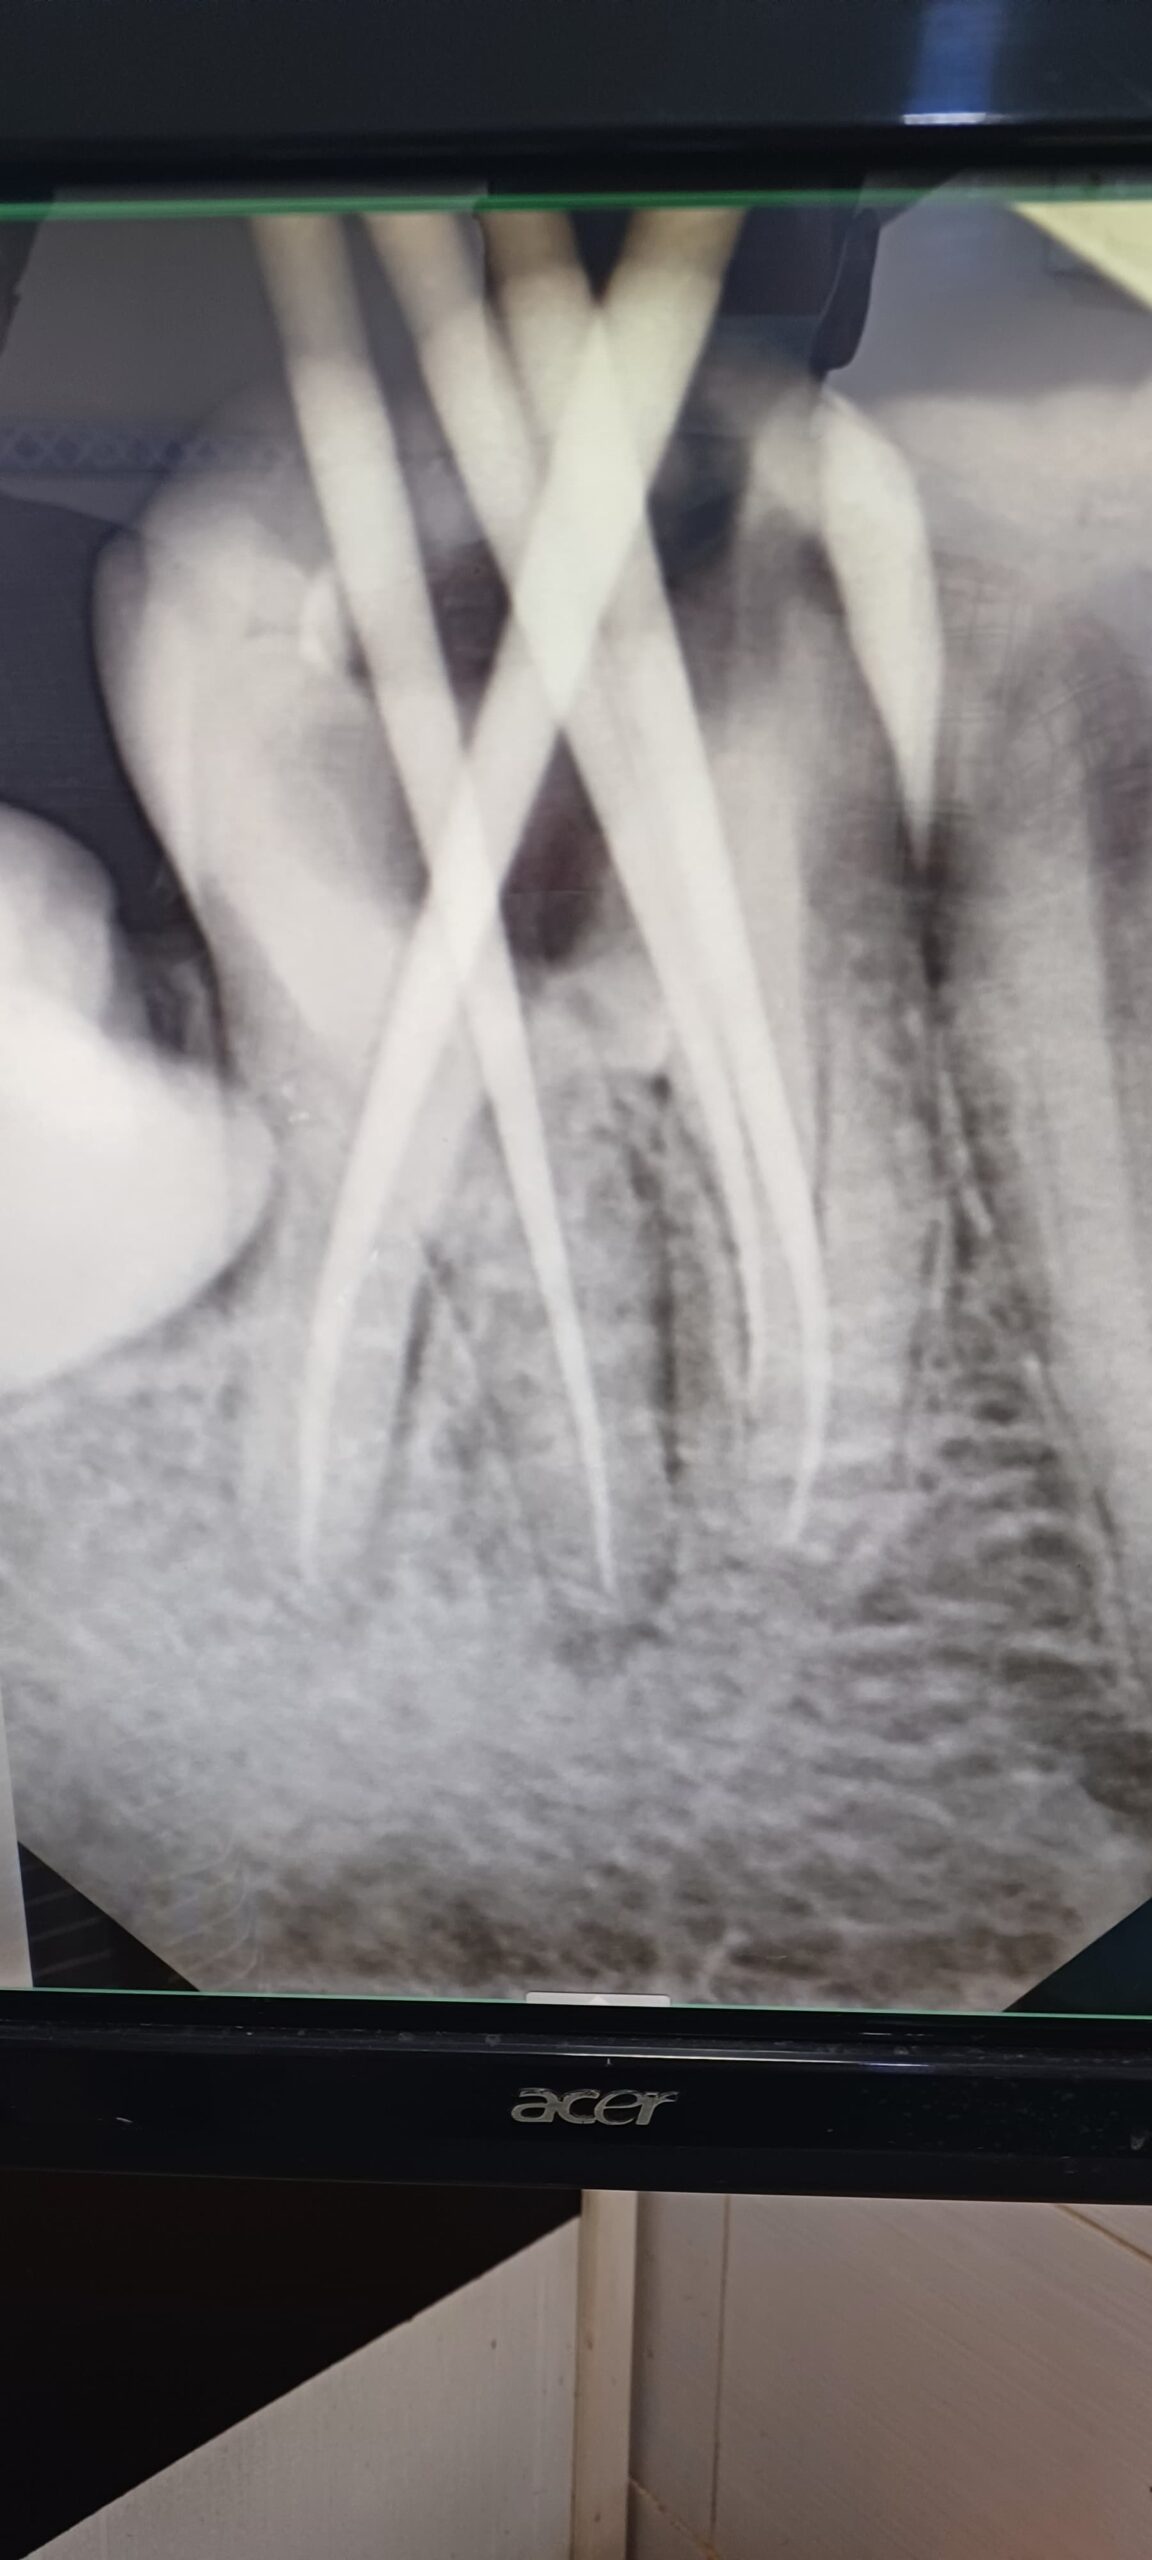

Gallery Home Gallery Pulpectomy Broken File Retrieval Root Canal Treatments Orthodontic Treatments Wisdom Teeeth Removal